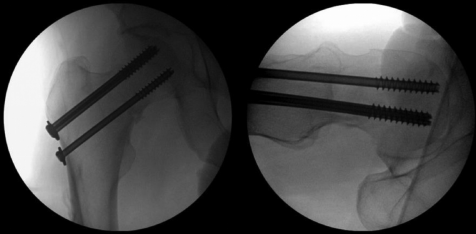

病例示例:股骨颈骨折空心螺钉内固定术

术前透视成像序列显示:患者为稳定性轻度外翻嵌插型股骨颈骨折,伴轻微股骨颈下段粉碎性骨折,矢状面未见台阶征或成角畸形(图8)。

术后影像显示空心螺钉固定位置安全,通过宽间距倒置固定模式对骨折端实现有效加压(图9)。

图9